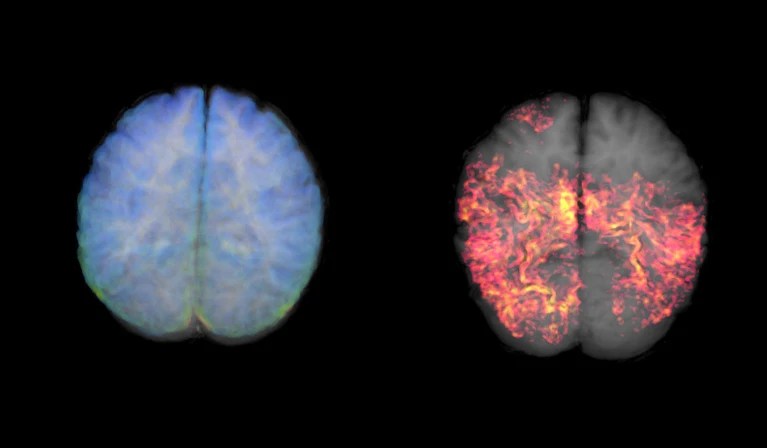

Hasta ahora, confirmar la presencia de las «huellas» biológicas del Alzheimer —las placas pegajosas de amiloide-β y los ovillos de proteína tau que matan las neuronas— era un desafío. Las únicas formas de detectarlas en un paciente vivo eran a través de una punción lumbar para analizar el líquido cefalorraquídeo, o mediante un escáner cerebral PET, una técnica de neuroimagen muy costosa y poco accesible.